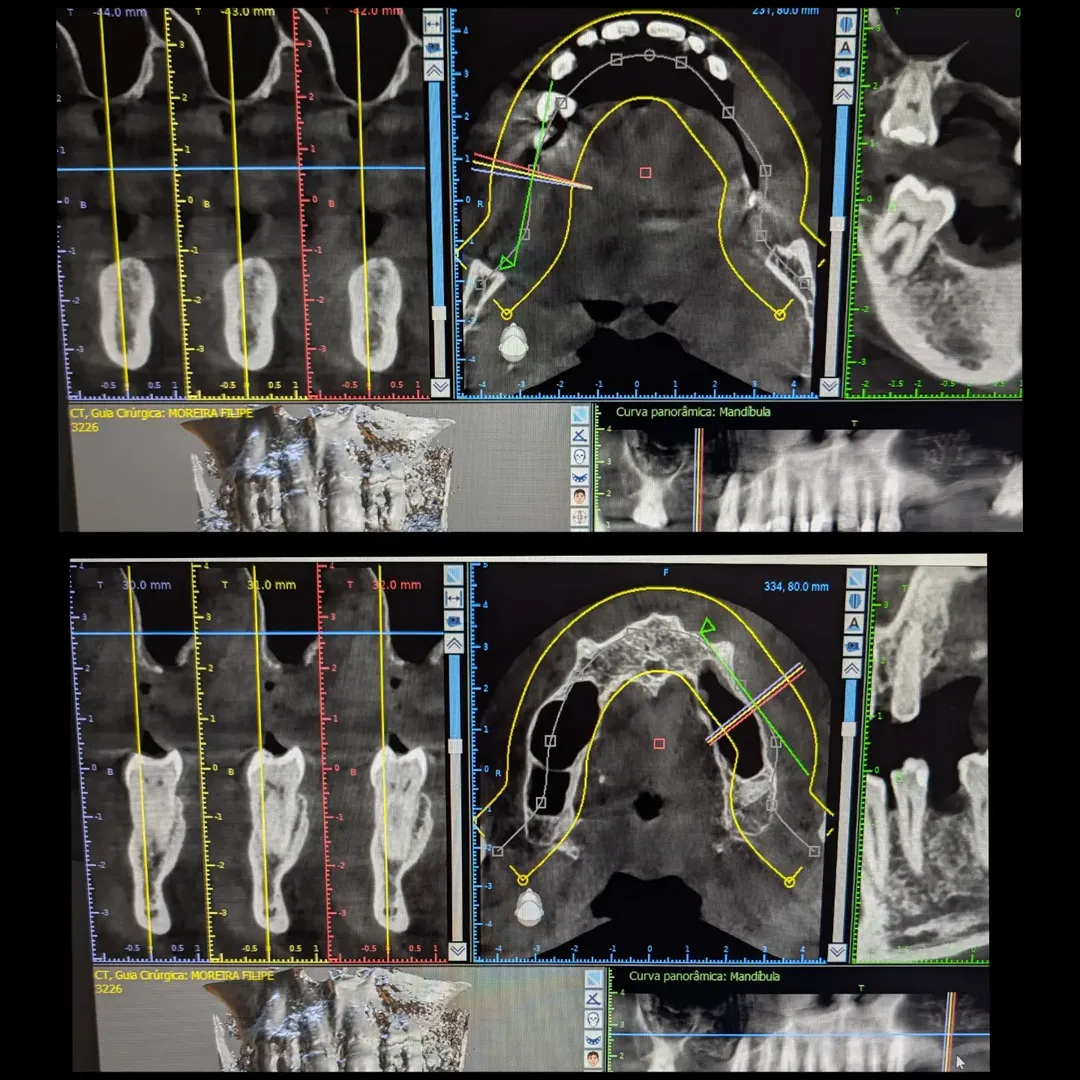

- Arcada inferior - Planeamento digital e cirurgia guiada: Realizei o planeamento digital com CBCT e scans intraorais, e avancei com cirurgia guiada para a colocação de 3 implantes, devolvendo a carga mastigatória total na arcada inferior.

O paciente apresentava ausências dentárias em ambos os quadrantes superiores e na arcada inferior, com múltiplos dentes comprometidos. A ortopantomografia e o CBCT confirmaram seios maxilares muito baixos, com osso insuficiente para a colocação de implantes nas zonas posteriores superiores.